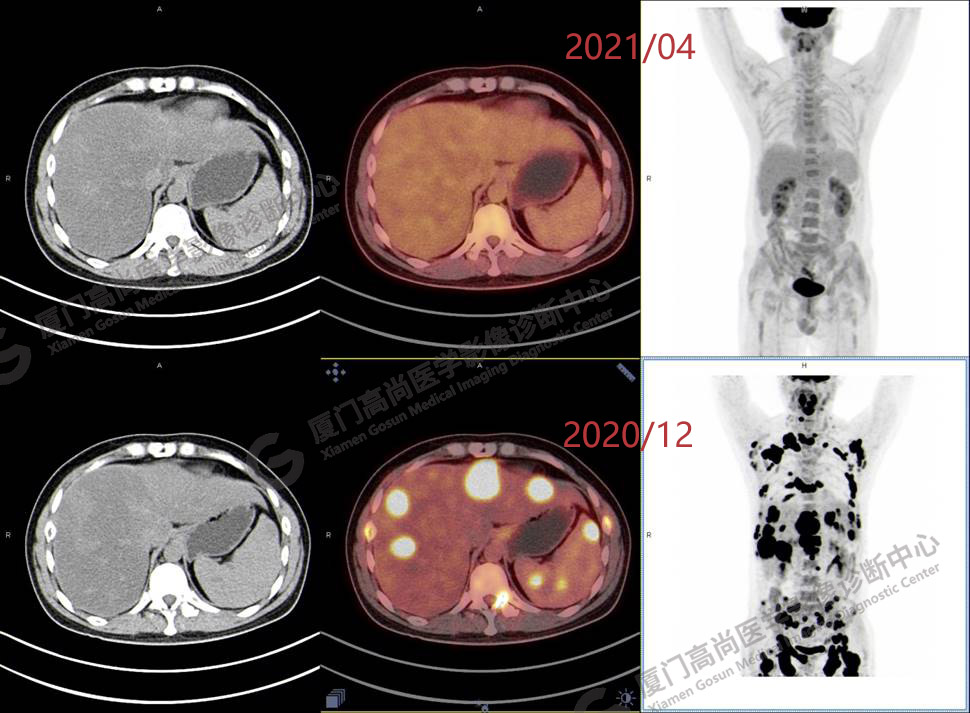

2020.12月本中心PET/CT示:全身多發(fā)腫大淋巴結(jié),代謝不同程度增高;肝臟多發(fā)稍高密度結(jié)節(jié)、脾臟多發(fā)稍低密度結(jié)節(jié),代謝異常增高;全身多發(fā)骨骼溶骨性骨質(zhì)破壞,代謝異常增高,胸2、腰1椎體病理性骨折,診斷為淋巴瘤。隨后,病理確診為彌漫大B細(xì)胞淋巴瘤。

患者化療4個療程后,于2021.04月返我中心復(fù)查,現(xiàn)患者本人已能自主行走,此次更是獨自一人來我中心復(fù)查PET/CT。檢查結(jié)果顯示:原全身多發(fā)病灶基本消失,且病灶代謝基本恢復(fù)正常。以下是患者PET/CT前后對比圖像:

PET/CT前后對比圖像1